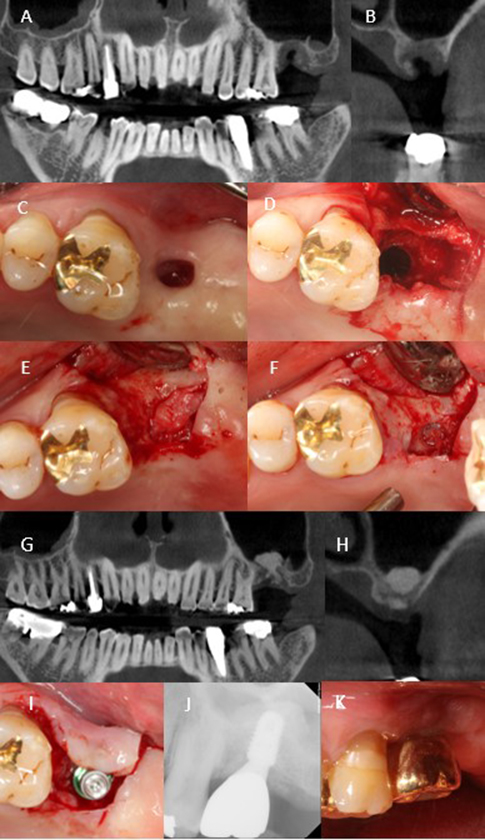

A 65-year-old male presented with an oroantral fistula at the site of a previously grafted tooth 27 extraction socket. The patient reported that bone grafting had been attempted at a local clinic but was complicated by postoperative infection and wound dehiscence. Clinical and radiographic examination confirmed communication with the maxillary sinus and exposure of infected graft material (Fig. 2A to 2D). Initial management involved thorough debridement, removal of the infected material, and reinforcement of the Schneiderian membrane with an absorbable collagen membrane. Primary closure was achieved using periosteal-releasing incisions to allow for soft tissue healing.

Eighteen months later, a re-entry surgery was performed. Flap elevation revealed that the sinus floor was partially closed with stable soft tissue coverage, although bone regeneration within the socket remained minimal. The Schneiderian membrane appeared intact and resilient, permitting transcrestal sinus floor elevation and simultaneous GBR to be performed under favorable conditions (Fig. 2E and 2F). A transcrestal sinus floor elevation was subsequently performed using 0.5 g of deproteinized bovine bone mineral (Bio-Oss; Geistlich Pharma AG) alongside simultaneous bone grafting using a 100 mg block-type xenograft (Bio-Oss Collagen; Geistlich Pharma AG) and an absorbable collagen membrane (Bio-Gide; Geistlich Pharma AG).

At 6 months postoperatively, a dental implant (TS III, Ø5.0 × 8.5 mm; Osstem Implant) was placed with adequate initial stability, and a healing abutment was connected to allow transmucosal healing. CBCT at that time revealed vertical bone regeneration, reaching a height of 9.9 mm, supporting successful implant placement and long-term stability (Fig. 2G to 2K). The prosthesis was delivered 5 months later after confirming an ISQ above 75. The implant has remained functionally stable and complication-free during 63 months of follow-up under regular maintenance.

Despite the unfavorable condition of sinus exposure due to prior infection, Case 2 exhibited partially preserved bony housing, providing a stable environment conducive to healing and favorable GBR outcomes.

Fig. 2

Clinical and radiographic treatment sequence of Case 2. (A, B) Initial cone-beam computed tomography (CBCT) showing an oroantral fistula and insufficient bone at the previously grafted tooth 27 site, (C, D) Intraoral view before treatment showing sinus exposure, (E, F) Re-entry at 18 months demonstrating partial soft tissue coverage of the sinus floor with an intact Schneiderian membrane, (G, H) Six-month postoperative CBCT showing vertical bone gain in both the sinus and socket compartments, (I) Placement of the implant fixture with sufficient initial stability, (J, K) Periapical radiograph and intraoral image at 63-month follow-up showing stable function and healthy peri-implant soft tissue.